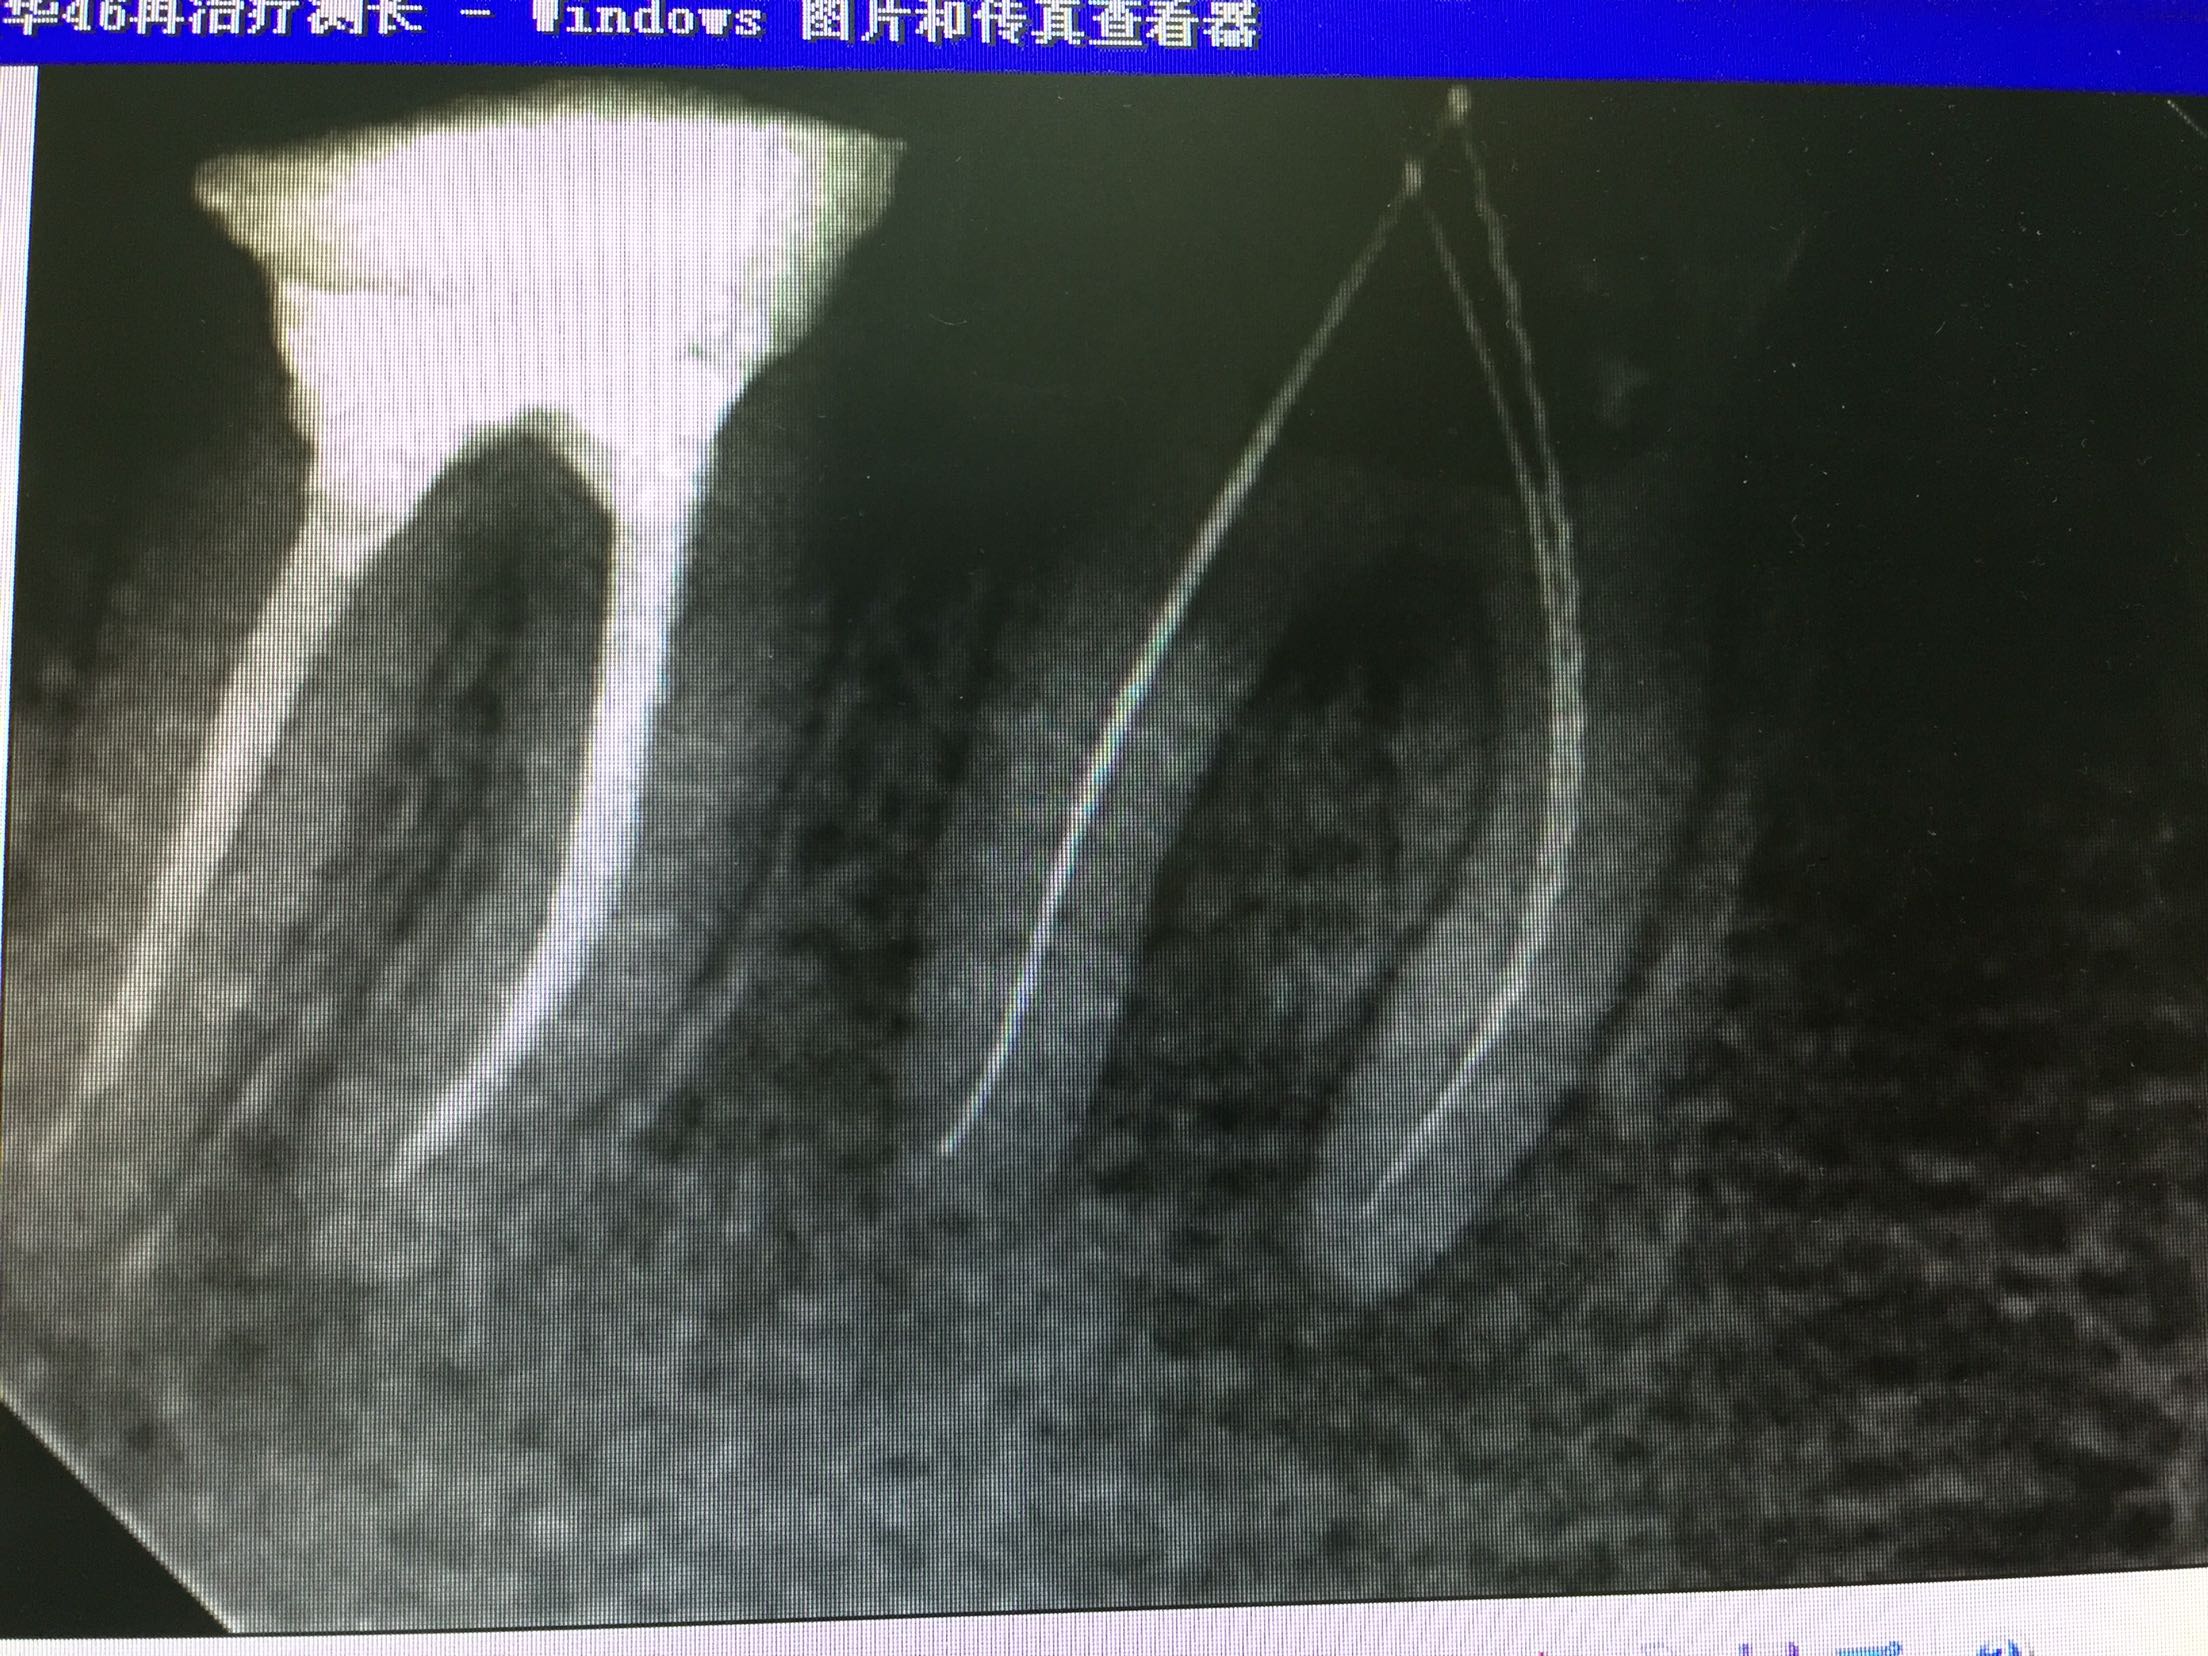

检查:47充填物存,46牙备后,充填物存,叩诊(+-),松动不明显,牙龈无明显红肿,冷诊(-)。X线示:46根尖区低密度影像,根充欠充,不密合。47根充后影像,根充可。

诊断:46慢性根尖周炎 治疗:46常规去除原充填物,拆根充,分步完成根管治疗。 转修复科进一步行修复治疗。

讨论:对于根管再治疗,要分析原来治疗失败的原因,再治疗时要解决这个问题,拆根充时要细心,避免将原根充物推出根尖孔。